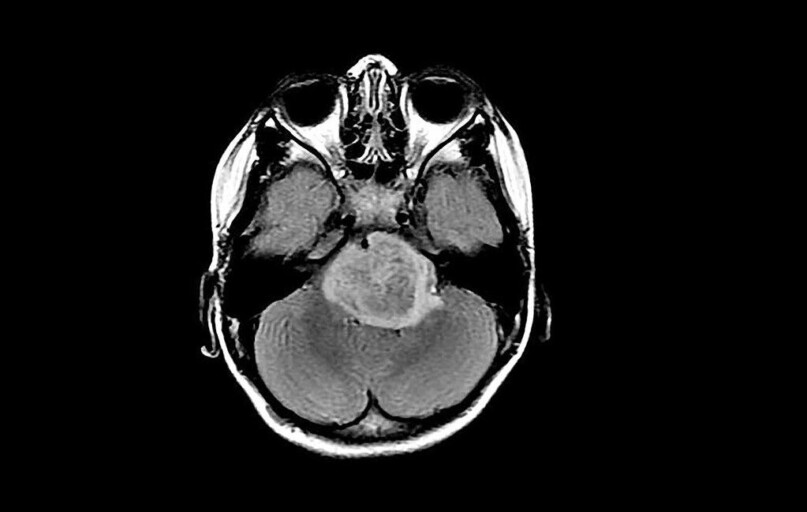

Jogailos universiteto (Lenkija) mokslininkai kuria naują, gerokai saugesnį vaistų pristatymo į smegenis būdą. Jų sukurta technologija leidžia cheminių preparatų dozes nukreipti tiesiai į naviką arba į smegenis per nosies ertmę. Taip mažinamas bendras toksinis poveikis organizmui ir atsiveria perspektyvos veiksmingesniam smegenų vėžio gydymui.

Iki šiol chemoterapija, taikant temozolomidą (TMZ), dažnai buvo siejama su sunkiais šalutiniais poveikiais, nes toksinis vaistas veikdavo visą organizmą, pažeisdamas ir sveikas ląsteles. Jogailos universiteto tyrėjų komanda suprojektavo biopolimerinį nešiklį, kuris vaistą pristato lokaliai ir palaipsniui, todėl nebereikia, kad jis cirkuliuotų visoje kraujotakos sistemoje.

Sukurtas preparatas gali būti vartojamas ir per nosį, gelinio aerozolio pavidalu. Tokiu atveju vaistas smegenis pasiekia per uoslės ir trišakio nervo galūnes, apeidamas kraujo–smegenų barjerą, kuris ilgą laiką buvo viena didžiausių kliūčių gydant centrinės nervų sistemos navikus.